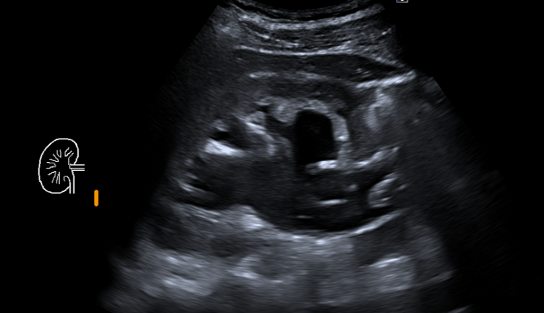

In diesem Fallbericht beschreiben wir einen 17-jährigen Patienten, der mit rez. ausgeprägten Koliken in unserer Abteilung vorstellig wurde. Initial erfolgte bei Hydronephrose °III und pos. Steinanamnese des Vaters eine CT-Abdomen nativ, welche bereits den V.a. einen retrocavalen Harnleiter rechts ergab. Eine Szintigraphie bestätigte eine urodynamisch relevante Obstruktion bei ausgeglichener Nierenfunktions. Bei Symptomatik erfolgte eine retrograde Ureteropyelographie mit JJ-Einlage. Im weiteren Verlauf wurde noch eine MRT-Angiographie durchgeführt, welche den Befund eindeutig bestätigte. Daraufhin erfolgte am 10.11.2025 die daVinci-assistierte Ureterureterostomie rechts in Linksseitenlage. Hierfür wurden 4 Arbeitstrokare und ein Kameratrokar verwendet. Die Gesamtoperationszeit lag bei 181 min, die reine Konsolenzeit bei ca. 100 min. Intraoperativ erfolgte ein JJ-Wechsel. Die Anastomose erfolgte mit einer 4.0 Quill-Naht in fortlaufender Technik. Der Blutverlust lag bei ca. 20 ml. Postoperativ waren die Schmerzen mit Novalgin gut beherrschbar. Die Entlassung erfolgte am 5. postoperativen Tag nach DK-Entfernung.